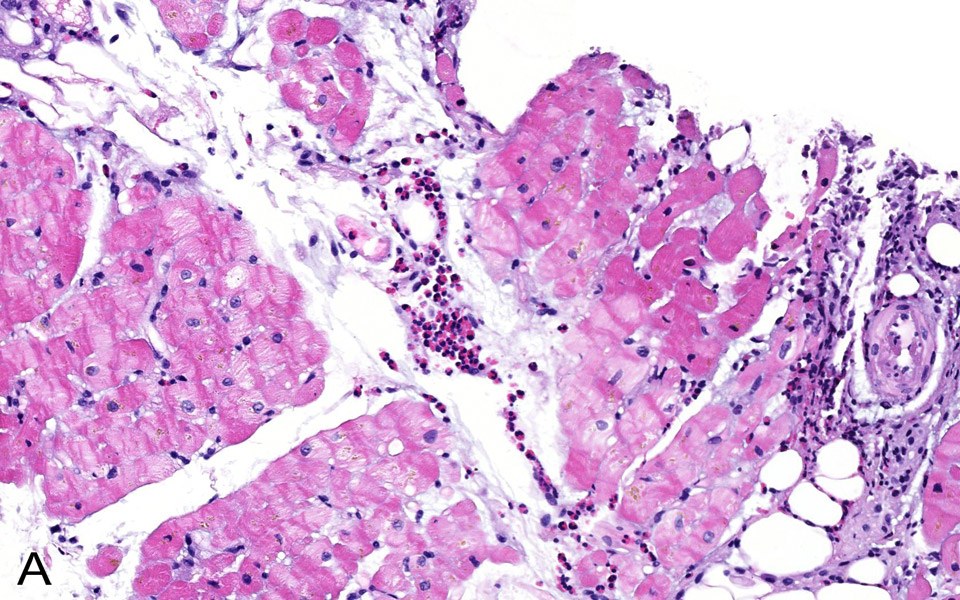

Figure 3A

Intramyocardic vessels showing luminal eosinophils which were also found in the surroundig interstitium and between the myocardial fibers (H&E stain, 100x).

A 76-year-old woman was admitted for atypical chest pain and fatigue of 10 days’ duration. The clinical findings were irrelevant except for epigastric tenderness. The electrocardiogram (ECG) showed a borderline 0.1 mV horizontal ST depression in V4-V5 and minor ST abnormalities in V6, II, III and aVF leads (fig. 1). The chest radiography was normal. Blood analysis disclosed pathological levels of troponin-I (6.1ug/L; normal <0.30), total creatine phosphokinase (424 U/L; normal <167), creatine phosphokinase MB isoenzyme (84.1 µg/L, normal <3.4) and lactate dehydrogenase (243 U/L, normal <232). The leukocyte count was elevated (16.7 G/L, normal 4.0–10.0). Transthoracic echocardiography (TTE) showed a hyperkinetic left ventricle with a thickened interventricular septum and minimal pericardial effusion. Non-ST segment elevation myocardial infarction was diagnosed on the basis of the association of chest pain and a further increase of troponin-I (peak value 13.7 µg/L). The emergency angiogram showed normal coronary arteries. In the meantime, haematological study revealed persistent leucocytosis (peak value 19.9 G/L) with 67% eosinophilia, corresponding to an eosinophilic count of 13.2 G/L, elevation of eosinophil cationic protein (ECP; >200 µg/L, normal <16.0), IgE (685 kU/L, normal <100) as well as serum tryptase (12.2 µg/L, normal 1.0–11.4). Cardiac magnetic resonance (CMR) was performed on a Siemens Avanto 1.5T (Siemens Medical, Erlangen, Germany). The cine and delayed enhancement images (DE-CMR) revealed only aspecific hypocaptation in the infero-basal portion of left ventricular myocardium, without late enhancement (fig. 2). As further workup we performed a myocardial biopsy demonstrating an important sub-endocardial eosinophilic infiltrate with fibrin deposition and focal extension into the myocardium (fig. 3 A, B). Numerous intra- and perivascular eosinophils were also present in the interstitium. An extended aetiological workup was performed. The patient had a history of recurrent sinusitis and allergy to pollen and asthma. A solid neoplastic process was ruled out by thoraco-abdominal CT scan. Screening for parasites in the serum and stools was negative, as were serological tests for antibodies to viruses and biopsy for a myocardial infection. Haematological screening showed normal beta2-microglobulin and vitamin B12, no FIP1L1-PDGFRA mutation and normal immunoelectrophoresis. The immunological workup for vasculitis (ANCA, antimyeloperoxydase and anti-proteinase 3) was negative. On the basis of asthma, recurrent sinusitis, hypereosinophilia and the results of the heart biopsy, Churg-Strauss syndrome was diagnosed (table 1). Pulse endovenous corticosteroid treatment (500 mg i.v. prednisolone) was started just after the cardiac biopsy. At day 1 levels of blood eosinophils dropped to 0.4 G/L and the ECP level returned to normal values. The hospital course was uneventful and 3 months later the patient was still asymptomatic with a normal eosinophil count on oral prednisone.

Cardiac involvement is one of the more serious manifestations of CSS [6, 7] and hypereosinophilic syndromes (HES) [8, 9], accounting for approximately one-half of deaths attributable to CSS (table 1). The eosinophil-mediated heart damage evolves through three stages: acute necrotic, intermediate thrombotic and fibrotic stage. The first corresponds to our case and is usually clinically silent.